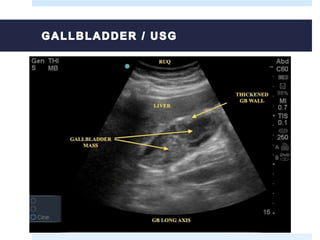

 Abdominal ultrasound (is the first to be performed after the patient any

symptoms or risk factors mentioned).

 Early-stage cancers, especially sessile polyps can not be seen.

 Typical image of gallbladder

cancer:

Focal or diffuse wall thickening

Intraluminal mass >2 cm arising from the

gallbladder wall

Hepatic mass that replaces or darkens the

bladder, commontly invades other organs

 Indicative findings suggesting that

the lesion is malignant:

Thickening of the wall (irregular and

aymmetrical) >1 cm

Nodular intraluminal mass or smooth, >1

cm, fixed to the wall of the bladder, which

does not move with the patient's

movements and has no acoustic shadow

CT and MRI may be useful in the diagnosis if ultrasound findings are indeterminate